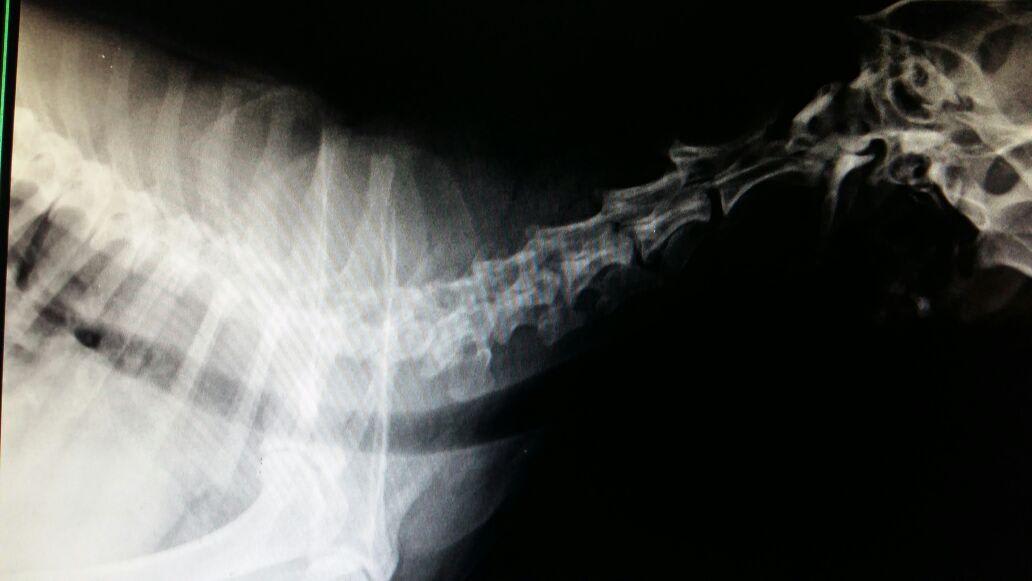

Hello. I have a female labrador named Lily, she's thirteen years old. She has been diagnosed with acute arthritis and adviced to be given painkillers and steroids. The medication begins today but we're concerned about the side effects. Please advice.

Hi there and thank you for using pet coach to address your concern. Before beginning steroids, I typically start joint supplementation and conservative management before resorting to steroids. Below are the things I currently recommend to combat the pain from arthritis: 1. Dasuquin for large dogs 2. Adequan injections 3. Cold laser therapy 4. Omega 3 fish oil 5. Pain relievers such as amantadine, gabapentin, methadone, and tramadol. If you really want to invest more money into arthritis management PRP injections can help quite a bit. I hope this helps! Please let me know if you have any other questions or concerns.